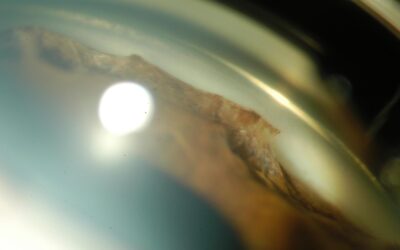

Synéchie dans un ICE syndrome

Le syndrome irido-cornéo-endothélial (ICE), qui englobe l’atrophie essentielle de l’iris, le syndrome de Chandler et le syndrome de Cogan-Reese (ou “iris nævus syndrome”), est le plus souvent unilatéral, non familial et survient typiquement chez la femme jeune. Le...